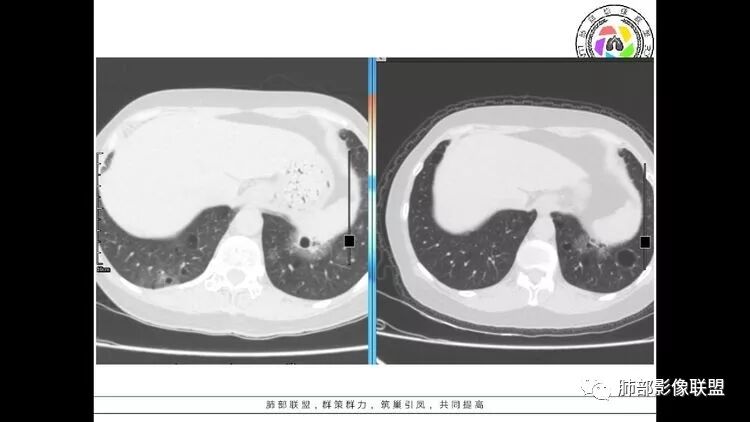

左肺下叶混杂密度病灶,其内可见空泡,周围ggo清楚,考虑浸润性腺癌。双肺散在多发薄壁囊腔和实性结节,以胸膜下及血管旁分布位于,气囊可见血管贴边征,双肺小叶间隔及中央间质增厚,局部可见磨玻璃影及树芽征,纵隔内淋巴结肿大,考虑LIP

综上,考虑左下肺浸润性腺癌+LIP

双肺多发大小不等囊腔,可见薄壁,部分囊腔内可见血管影,伴双肺多发结节,结合患者眼病及类风湿病史,考虑LIP可能大。另左肺下叶磨玻璃结节,边界清晰,内可见空泡,伴纵膈多发肿大淋巴结,不除外浸润性腺癌可能。